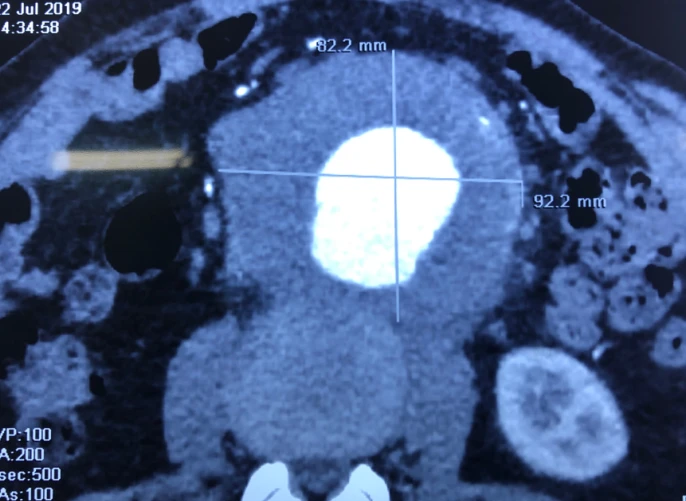

Các bác sĩ (BS) khoa Phẫu thuật tim - mạch máu BV Bình Dân TP.HCM vừa phẫu thuật cấp cứu thành công trường hợp túi phình động mạch chủ bụng kích thước 9 x 8,6 cm cho ông NVV (57 tuổi, ngụ Đắk Lắk).

Tại đây, ông V. và gia đình được BS giải thích túi phình của ông có kích thước như một trái bưởi nhỏ, nếu vỡ sẽ gây một lượng lớn máu ào ra ổ bụng, nguy cơ tử vong lên đến trên 90% nên can thiệp sớm lúc nào hay lúc đó.

Túi phình động mạch chủ bụng như quả bưởi sắp vỡ. Ảnh: BVCC

Ông V. ngay lập tức được chuyển lên phòng phẫu thuật. Ca mổ nhiều thách thức vì khối phình khổng lồ không chỉ choán chỗ trong ổ bụng mà có phản ứng viêm dính vào đốt sống thắt lưng (đốt sống L1, L2) gây đau lưng. Ngoài ra, cổ túi phình nằm quá sát động mạch dưới thận, nếu cầm máu sai chỗ có thể gây suy thận vĩnh viễn do thiếu máu nuôi.